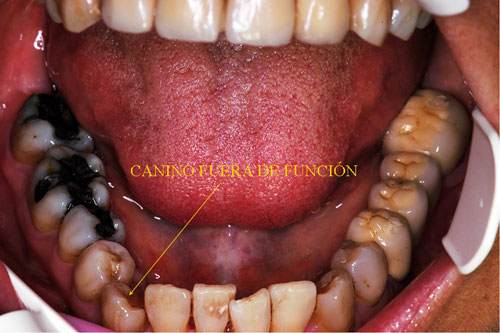

Canino que no cumple su Función Desoclusiva

En O.R.C. el Canino no funciona